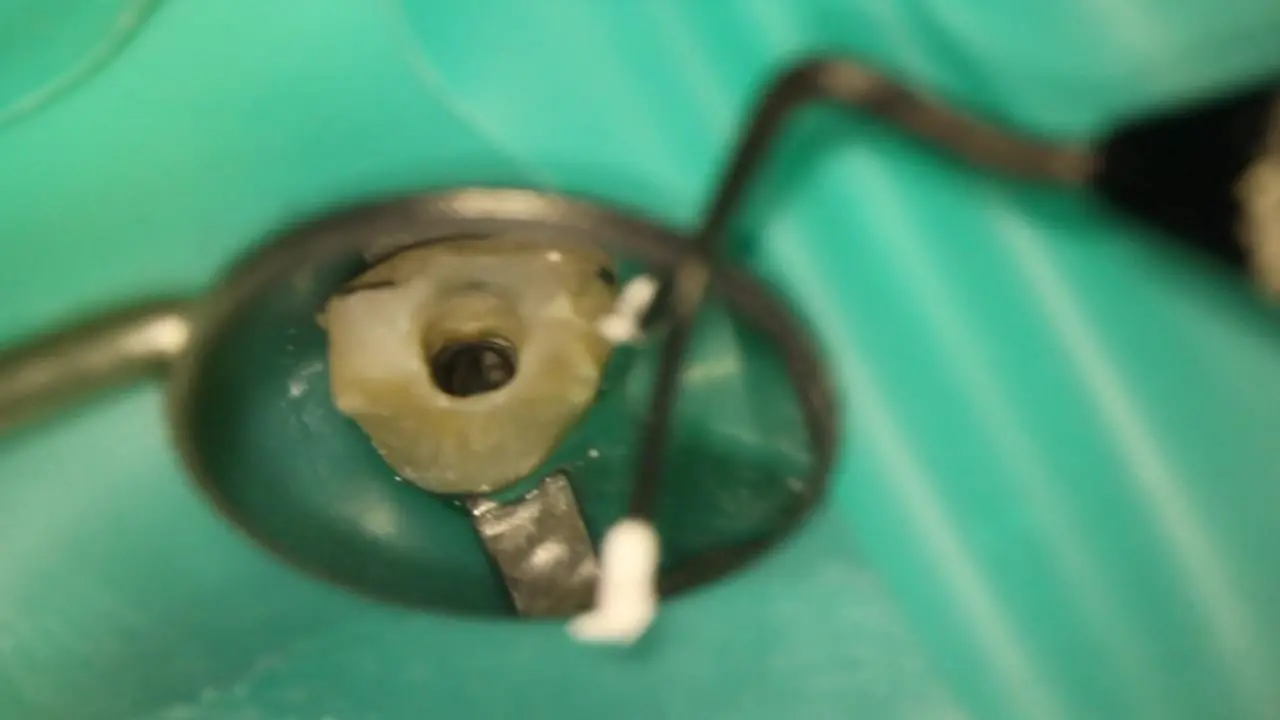

Діагностика і лікувальна тактика: коли можна не втручатись в пульпу, коли можна видаляти її частково і що робити, коли пільпа загинула. Часткова і повна пульпотомія: коли і як це робити? Що робити коли пульпа загинула повністю? Апексифікація і апексогенез, гідроксид кальцію і пробка з МТА. Останні регенераторні тенденції в ендодонтії. Реваскуляризація - що це і коли варто робити?